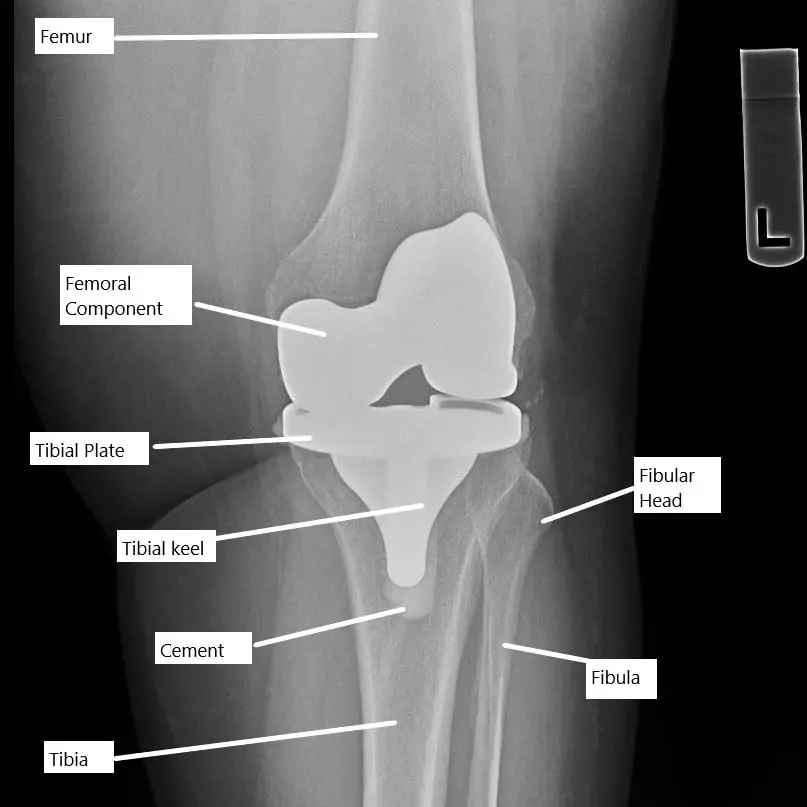

X-ray showing a total knee replacement.

The knee joint is a hinge joint that allows for the bending (flexion) and straightening (extension) of the leg. Knee replacement surgery involves replacing the damaged knee surfaces with a metal and plastic prosthesis to restore mobility. Normally, the knee can flex from 0 degrees (fully straight) to about 135 degrees (fully bent). After surgery, a proper range of motion (ROM) is essential for day-to-day activities, such as walking, sitting, or climbing stairs.